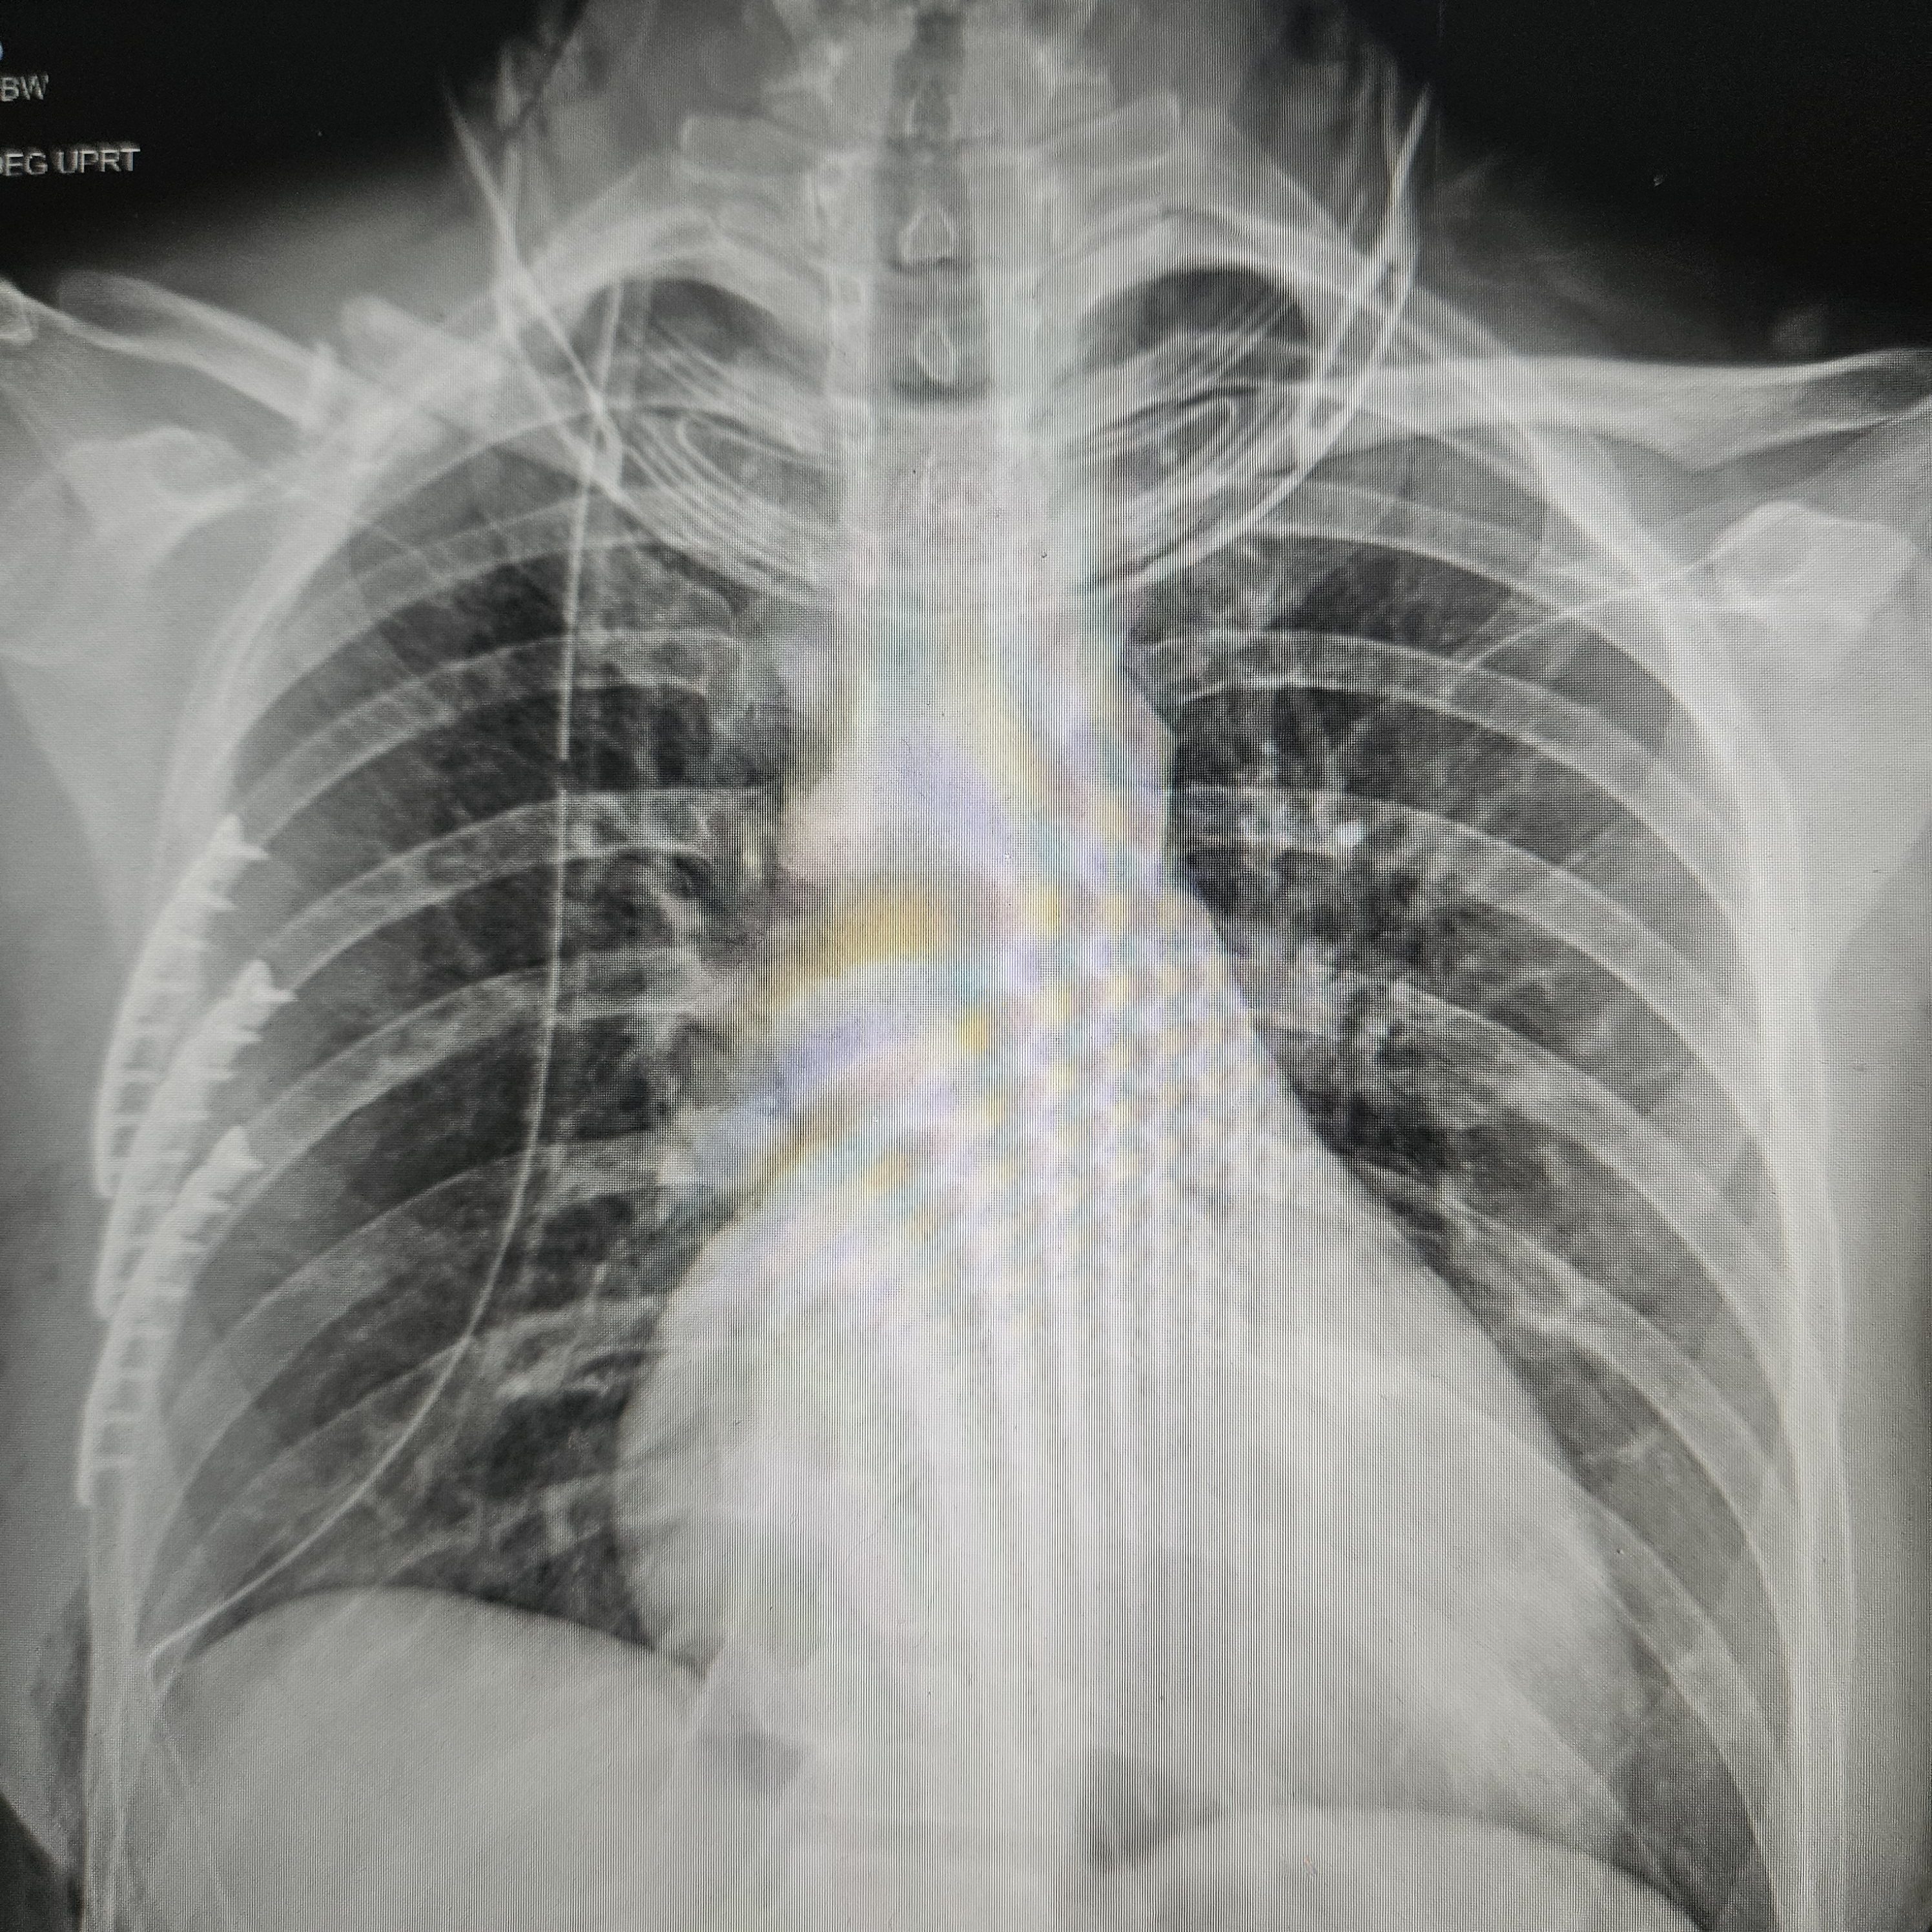

My husband was walking up to the trauma bay as I was being unloaded from the ambulance. I was happy to see him as I’m sure he was happy to see me in a stable condition. I may have been a little too happy after the pain medication I received enroute, joking and bantering with the medics. I was wheeled into the Emergency Department where the entire trauma bay was lined with hospital staff dressed in their yellow gowns and gloves also unaware of the extent of my injuries. They transferred me onto the hospital bed and immediately placed a rigid neck brace on in exchange for the softer version I had in transit. I knew my bike clothes were a goner. They graciously asked if there was an easy way to remove my heart rate monitor so they didn’t have to cut it off. I appreciated that. All the staff were then working in sync to complete their head to toe assessment. There was so much happening all at once and yet all I was doing was laying there: One provider was looking in my right ear while another was performing an ultrasound on my abdomen, and another assessing my leg wounds. I hear someone say “x-ray” followed by the beep of the machine shooting. Someone else was asking me questions about what happened and what I was feeling. There was a short argument over where my helmet was as the providers wanted to map out the damaged sites. Meanwhile exam findings were being yelled out to document. I hear someone say “right pneumothorax” (air trapped around the lung space). I immediately became nauseated and frantically asked if I would need a chest tube. Thankfully one of the workers noticed my distress and assured me that the pneumothorax was small and I wouldn’t need a chest tube for now (I later would).

As soon as they finished their initial assessment I was taken for a full body CT scan, then another CT, and then an MRI of my head and neck. It should have been a bigger red flag to me as to why they were looking at my neck so closely. But I was just at the mercy of the gurney. What ended up being hours felt like minutes. I gathered as much information as my brain would let me. Once all the scans were complete, the extent of my injuries were confirmed to be a broken right clavicle, four broken ribs (ribs #4-7), lung contusions, small hemopneumothorax (blood and air trapped around the lung), large right gluteal hematoma, and scattered road rash down the right side of my body. I asked if I could have the neck collar off to which the response was Neurosurgery needed to see me. At that point I put the pieces together that something was wrong with my neck. The good news was Neurosurgery came quickly and confirmed that I didn’t break my neck. The bad news was that I herniated a disc which was pressing on my spinal cord. That was the last I saw and heard from Neurosurgery during my hospitalization. I wasn’t told of the concussion diagnosis until later. I initially thought I lucked out by not getting one but it was so obvious that I had a concussion that it just wasn’t said out loud. My concussion symptoms became much more pronounced in the following weeks.